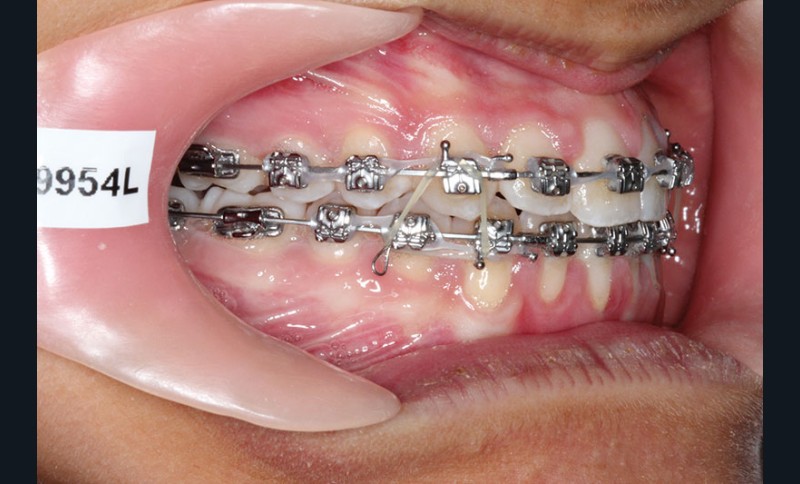

1re phase : recul des secteurs latéraux mandibulaires avec le Motion Classe III Carriere (fig. 4 à 6)

Nous mettons en place des bras latéraux Motion associés à des élastiques intermaxillaires ancrés sur des brackets sur 17 et 27 et une gouttière thermoformée maxillaire portée jour et nuit :

• 1er mois : élastiques 6 oz. 1/4”

• 2e mois et suivants : élastiques 6 oz.1/4“

L’objectif de cette étape est d’obtenir un recul des secteurs latéraux mandibulaires afin de positionner les molaires et canines en classe I et de réorienter le plan d’occlusion en haut en avant.